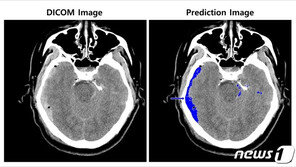

수분내 정확한 진단과 적절한 처치가 이뤄지지 않으면 심각한 후유증이 남거나 최악의 경우 사망에 이르기도 하는 ‘뇌출혈’을 인공지능(AI) 기술을 통해 빠르고 정확하게 진단할 수 있는 길이 열릴 전망이다. SK㈜ C&C는 ‘뇌출혈 영상 판독 AI 모델’이 의료 기기 제조 및 …